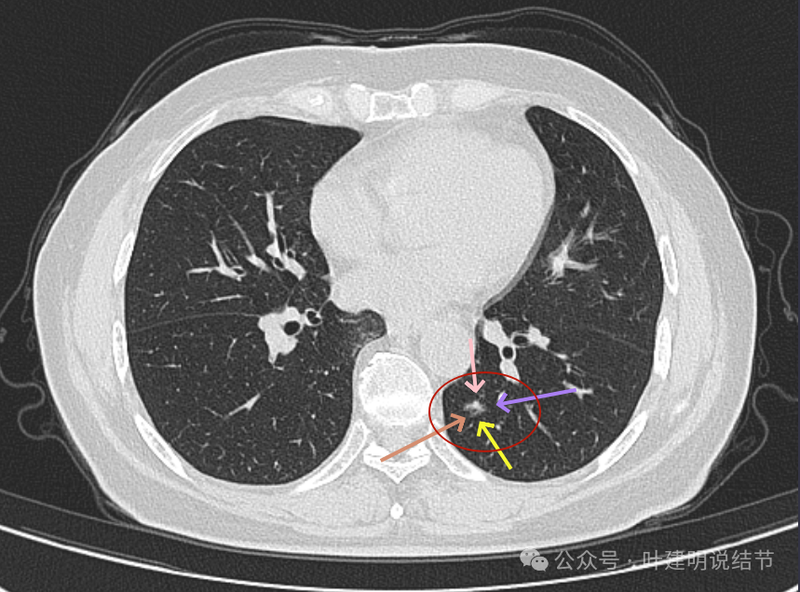

灶内细支气管扩张、边缘毛刺、虽小却有明显分叶征、整体轮廓与边界清楚、实性成分明显。